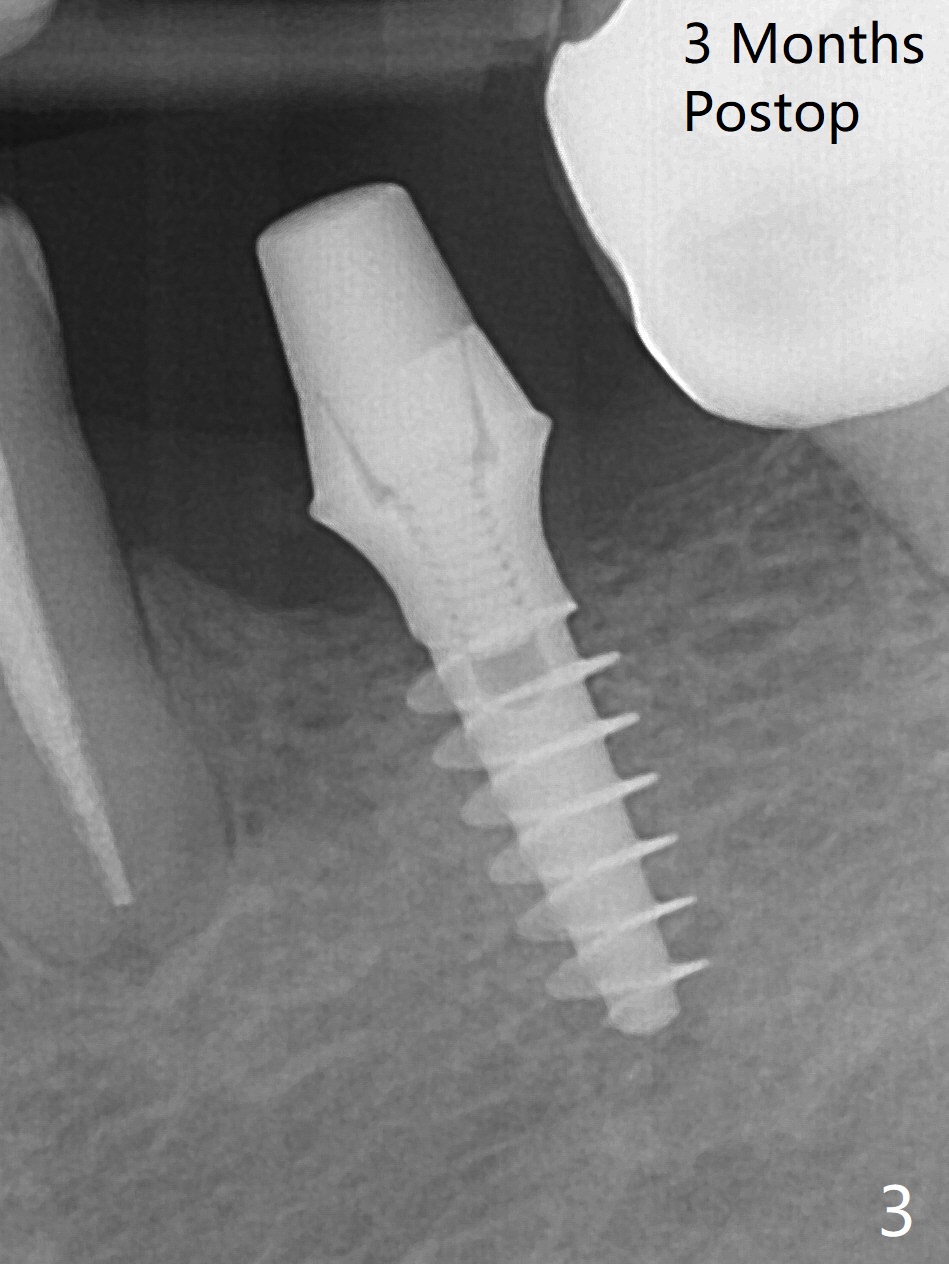

After finishing osteotomy at #19 according to IS drill sequence for 4x10 mm implant except cortical tap, a 4x9(2) mm Magicore is placed with ~ 50 Ncm (Fig.1). A 4.5x3 mm solid abutment is placed to check occlusion (Fig.2). There is discrepancy in osteotomy depth probably due to difference between the implant systems or overprep for subcrestal placement (narrow ridge, Fig.2 *). The implant could be 2 mm longer or the cuff could be longer (3 mm instead of 2 mm). The implant with 4.5x3 mm solid abutment is stable for impression nearly 3 months postop (Fig.3). Appreciate the distinct thread pattern of Magicore 3 months 1 week postop, immediately post cementation (Fig.4). Bone density increases 7 months post cementation (Fig.5 *). There is less likely implant fracture associated with a 1-piece one than a 2-piece one when a narrow one is placed in the narrow ridge.